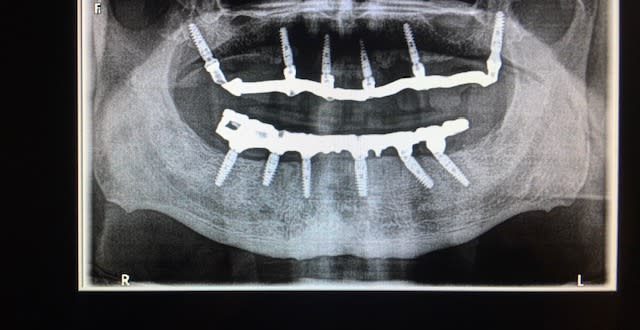

enlaye, un multi-unit avec une angulation + importante et une hauteur gingivale + importante aussi pourrait te permettre construire une prothèse avec une accessibilité de nettoyage de cette zone.

L'avantage de tout faire soi--même c'est qu'on pose les implants en fonction de la future prothèse et pas l'inverse en essayant d'adapter la prothèse à la position des implants...

Là, c'est ingérable en l'état.

Donc il n'y a que deux solutions: soit l'implanto dépose et refait en fonction d'une maquette, soit il rembourse la patiente et passe la main. Mais ne te lance pas dans la prothèse là dessus. Sinon, la bave aux lèvres, tu risques de l'avoir mais pas par béatitude neo provençale ;))

ok , mais à enfouir plus , je ferais un pilier dans l autre sens , comme sur le dessin .

normalement sur un cas comme celui ci pour éviter les problèmes supplémentaires le MU est anti rotationnel

le MU a plusieurs positions dans l'implant du fait de l'hexagone interne , donc le "spécialiste poseur " doit avoir un MU fantôme le jour de la pose pour torquer l'implant, vérifier l'émergence du MU donnant une bonne angulation de MU CQFD

ah ouiii , bien sur , tu veux dire que lorsqu il visse l implant , il doit finir le vissage EN FONCTION de l angulation du MU prédéterminée placée au bon endroit par rapport aux autres implants .

quitte a mettre le MU direct et tourner l implant avec pour etre pil poil .

voila exactement la même position de l'implant mais avec une angulation + importante à gauche

OUI !! en procédant de la sorte aucun risque d'erreur ; tu gères la sortie du MU au 1/3 de tour près , en conclusion le poseur ne s'intéresse pas à la prothèse !!! dommage !!

sur ce cas si tu ne fais pas comme je te dis à la pose de 36-37 , tu as deux chances sur 3 de te retrouver dans ta situation

Dans ton cas pourquoi tu les a posés de traviol ( 36 , 37 ), pour favoriser la longueur ? En rajouter des plus courts tu ne pouvais pas je suppose . Pb de largeur de cretes ?

ils ne sont pas de traviol !!

ils sont mésialés pour 2 raisons:

-axe qui facilite le vissage et hauteur du tournevis/ max sup

-insertion du bridge beaucoup plus facile si le MU est légèrement incliné en mésial